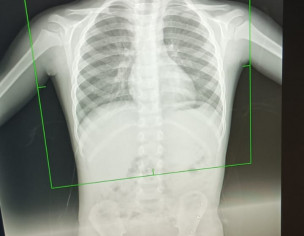

Asking for Other, Male, 4 years old, Okara

AOA Got this xray done for my son. He has cough and flu. Is it normal.

yes

but detail history required book consultation for proper management

yes seems normal